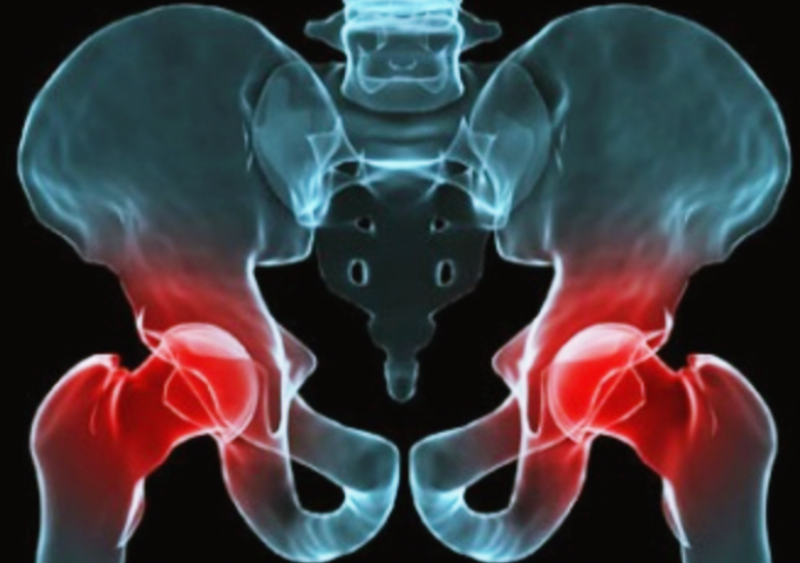

고관절이란 골반과 대퇴골을 잇는 관절을 의미하는데요. 다리를 골반에 연결시켜 걷거나 달리는 것을 가능하게 합니다. 그렇기 때문에 고관절에서 소리가 나거나, 절뚝거리거나, 통증이 나타날 수 있는데요.아래에서 고관절 통증 증상 9가지 및 예방법에 대해 자세하게 알아보는 시간을 가지겠습니다.

6. 퇴행성 고관절염

퇴행성 고관절염은 관절 부위의 연골이 닳아 고관절이 관절염으로 인해 손상되는 질환인데요. 우리나라 같은 경우에는 대퇴골두무혈성괴사, 외상 및 골절, 비구이형성증, 선천성 고관절 탈구 등의 후유증으로 발생하는 이차성 퇴행성 고관절염이 흔하게 나타납니다.